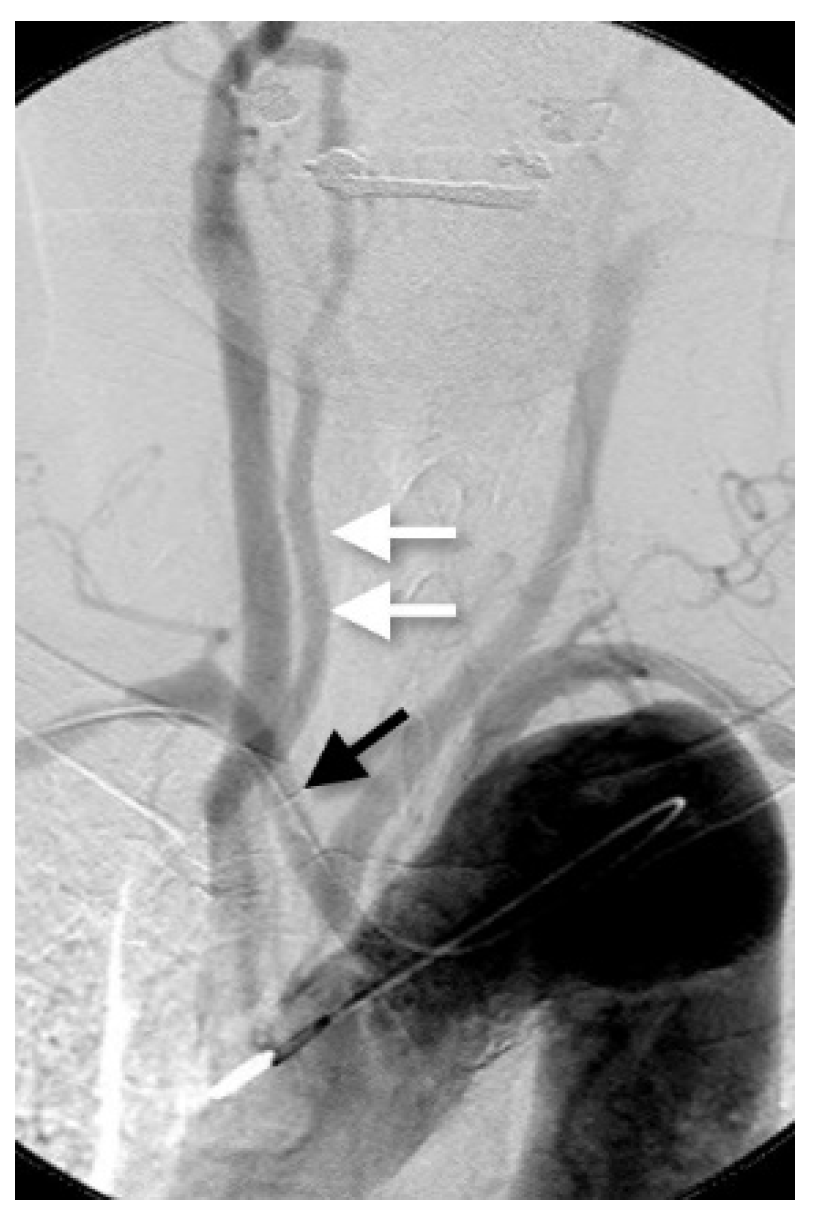

Figure 5.

Right VA originating from the common carotid artery with RSCA. Anteroposterior view on aortography shows the RVA arising from the right common carotid artery (double white arrow). An aberrant RSCA is also detected (black arrow).